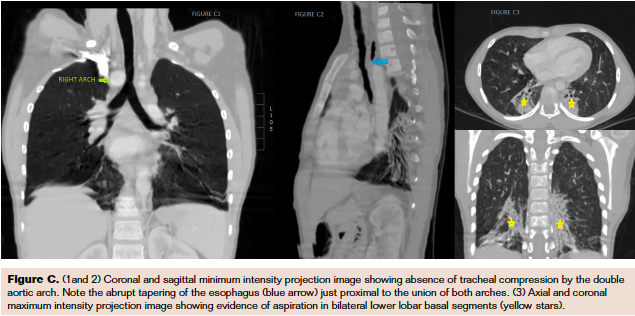

Her physical examination and electrocardiogram results were essentially unremarkable. Chest x-ray was suggestive of right aortic arch with consolidation in the right lower zone. Echocardiogram did not reveal any intracardiac lesion but raised suspicion of abnormality of aortic arch—presence of 4 neck vessels instead of the typical 3 vessels. Computed tomography (CT) angiogram was subsequently done, and it revealed the presence of double aortic arch (Figure A), with a larger right-sided arch (blue arrow) and smaller left arch (green arrow) joining to form the descending aorta (grey arrow). The right subclavian and common carotid arteries arose from the right arch (Figure B2) and, similarly, left subclavian and common carotid arteries from the left arch (Figure B1). A sudden taper (blue arrow in Figure C2) in the esophageal caliber was noted, suggesting esophageal compression, which may have exacerbated the respiratory symptoms.

CT also showed bilateral lower lobe consolidation (yellow stars in Figure C3). In view of her symptoms, surgery is planned with an aim to resect the lesser of the arches.